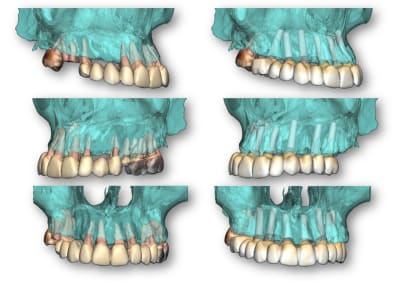

Vous avez constatés que dans ma conception des guides le support osseux est privilégié.

3 raisons principale, il me semble impératif de préparer le support osseux avant de poser et j'ai pu observer dans des cas d'édentations qui ont plusieurs années des tissus fibreux sont à retirer, la levée du lambeau permet de réaménager les tissus et obtenir la laxité du conjonctif pour recouvrir les ROG.

Le flapless me semble plus un argument pour donner illusion que l'implantologie peu s'affranchir de faire de la chirurgie.

Le positionnement osseux donne toute la liberté de planifier librement les réhabilitations globales.

Un exemple d'un cas plébiscité pourtant lacunaire

j'y vois des greffes de sinus en vu d'une MCI se qui implique environ 6 mois d'attente avec un antago précaire.

la conservation des dents résiduelles pour positionner le guide conduit à une répartition non équilibrée des implants

Ce qui est prévu 9 implants

résultat, seul 6 implants mis en charge

Pour conclure avec ce cas qui n'a suscité aucun commentaire, voici celui qui accompagnait

la vidéo d'où sont extraites les photos : "Affaire du jour. Une partie du cours de protho commence dans 2 semaines. Apprenez à simplifier les cas d'implant en arche complète de façon prévisible.

Concept star inspiré par..."

Son auteur propose une formation de simplification en réhabilitation totale de maxillaire en prothèse implanto-portée e présentant un cas qui démarre avec 11% d'échec implantaire.